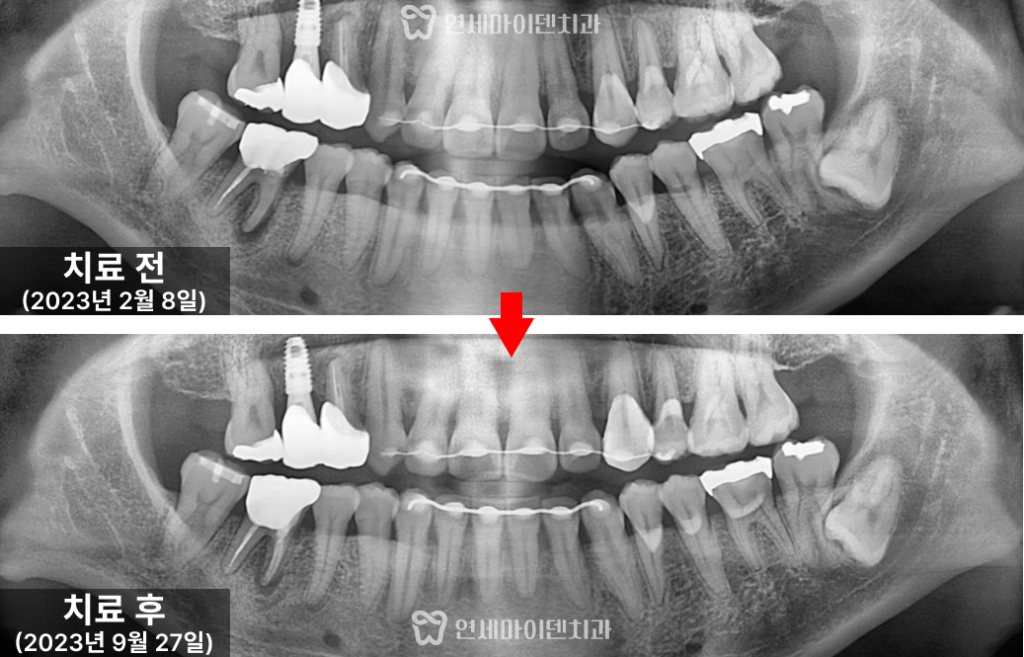

성공적으로 통증이 해소되며 기능을 회복했습니다.26번 치아 — 발치 즉시 임플란트

그러나 바로 뒤쪽의 #26번 치아는 상황이 달랐습니다.

보철물을 제거하자 내부에서 출혈이 계속되어 CT를 재확인했더니

구개측 뿌리(perforation)가 뚫린 상태였습니다.염증으로 인해 주변 뼈 손실이 심했고,

이미 MTA(특수 치근 수복재)를 적용하기엔

시기를 놓친 상태였습니다.이 경우 선택지는 두 가지입니다.

- 뿌리 절제술로 일부 뿌리만 남기는 방법

- 발치 후 임플란트 식립

환자분과 충분히 상담한 결과,

발치 즉시 임플란트를 선택하셨습니다.수술은 뼈 보존을 고려해 즉시 식립 후

안정적으로 골유착을 유도하였고,

수술 부위의 잇몸도 건강하게 치유되었습니다.

자연스러운 형태로 제작해서 올려주었습니다.치료 경과 및 예후

3년간의 추적 관찰 결과, #26번 임플란트는

주변 잇몸과 뼈의 안정성이 매우 양호한 상태로 유지되고 있습니다.#25번 재신경치료 부위 역시 염증이 완전히 소실되어,

통증 없이 자연치아처럼 사용 중이십니다.치료 전에는 불편감이 지속되던 부위가 현재는 완전히 회복되어

식사 시에도 전혀 불편함이 없다고 말씀하셨습니다.